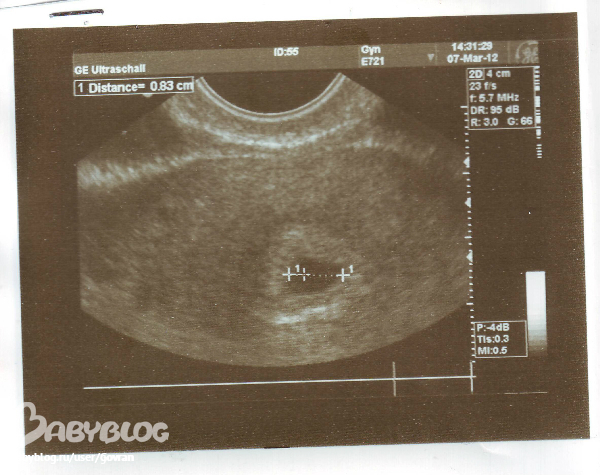

Вот судя по этому фото мерили по внутренней стороне

вот это черное пятно и есть эндометрий, в котором находится малыш... на моих снимках его еще не видно.. вот если мерить четко по краям черного пятна - то это внутренняя сторона эндометрия, а по её краям есть как светлая оболочка...(где я поставила красные крестики).... так вот её края это наружняя сторона... и вот по каким мерить правильно не понятно....